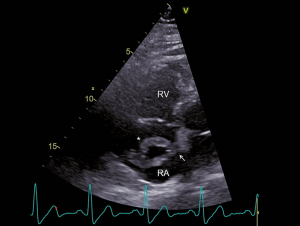

Ein 52-jähriger Patient musste sich wegen eines bronchialen Plattenepithelkarzinoms einer linksseitigen Unterlappenresektion unterziehen. Einige Tage postoperativ klagte der Patient plötzlich über starke Schmerzen im rechten Bein. Ferner bestand eine zunehmende Dyspnoe. Es zeigte sich im ischämischen rechten Bein ein ausgedehnter arterieller Gefässverschluss, welcher durch einen komplexen notfallmässigen Eingriff mit Thrombendarterektomie und Thrombektomie behandelt werden konnte. Die weiteren Abklärungen ergaben den Nachweis von tiefen Beinvenenthrombosen und von ausgedehnten beidseitigen Lungenembolien. Im Labor zeigte sich eine Thrombozytopenie und es wurde die Diagnose einer heparininduzierten Thrombozytopenie Typ II gestellt. Entsprechend wurde die Antikoagulation auf Bivalirudin umgestellt. Im Rahmen der Untersuchungen wurde eine transthorakale Echokardiographie durchgeführt. Hierbei zeigte sich ein dilatierter, exzentrisch hypertropher rechter Ventrikel (Abb. 1) und es fanden sich Zeichen einer ausgeprägten pulmonal-arteriellen Hypertonie (Abb. 2). Im rechten Vorhof zeigte sich ein grosser Thrombus, welcher am interatrialen Septum adhärent zu sein schien (Abb. 3). Ein Teil des Thrombus prolabierte durch die Trikuspidalklappe in den rechten Ventrikel (Abb. 4). Es wurde interdisziplinär entschieden, den grossen ‘Thrombus-in-Transit’ nach Stabilisierung des Patienten operativ zu entfernen. Die intraoperativ durchgeführte transösophageale Echokardiographie liess erkennen, dass der Thrombus nun durch ein persistierendes Foramen ovale (PFO) in den linken Vorhof prolabierte (Abb. 5). Bei der operativen Entfernung zeigte sich, dass der Thrombus in Fäden der Valvula Eustachii verfangen war (Abb. 6), was eine weitere Migration des Thrombus verhinderte. Der Anteil, welcher durch das PFO prolabierte, liess sich ohne Widerstand herausnehmen. Nach Entfernung des Thrombus wurde das Foramen ovale verschlossen. Die Operation verlief erfolgreich. Nach initial protrahiertem Verlauf erholte sich der Patient sehr gut und es zeigte sich eine deutliche Regredienz der pulmonal-arteriellen Hypertonie. Die Antikoagulation mit Bivalirudin wurde in der Folge auf Marcoumar umgestellt; es kam zu keinen weiteren thromboembolischen Komplikationen.

Abb. 3: RV-modifizierter apikaler Vierkammerblick Im rechten Atrium zeigt sich ein grosser, zweischenkliger Thrombus (*), welcher am interatrialen Septum adhärent zu sein scheint (Pfeil). RV = rechter Ventrikel und RA = rechtes Atrium.

Abb. 4: RV-modifizierter apikaler Vierkammerblick Erneute Darstellung des grossen rechtsatrialen Thrombus (*), wobei in diesem Bild der grössere der beiden Schenkel durch die Trikuspidalklappe in den rechten Ventrikel prolabiert (Pfeil). RV = rechter Ventrikel und RA = rechtes Atrium.